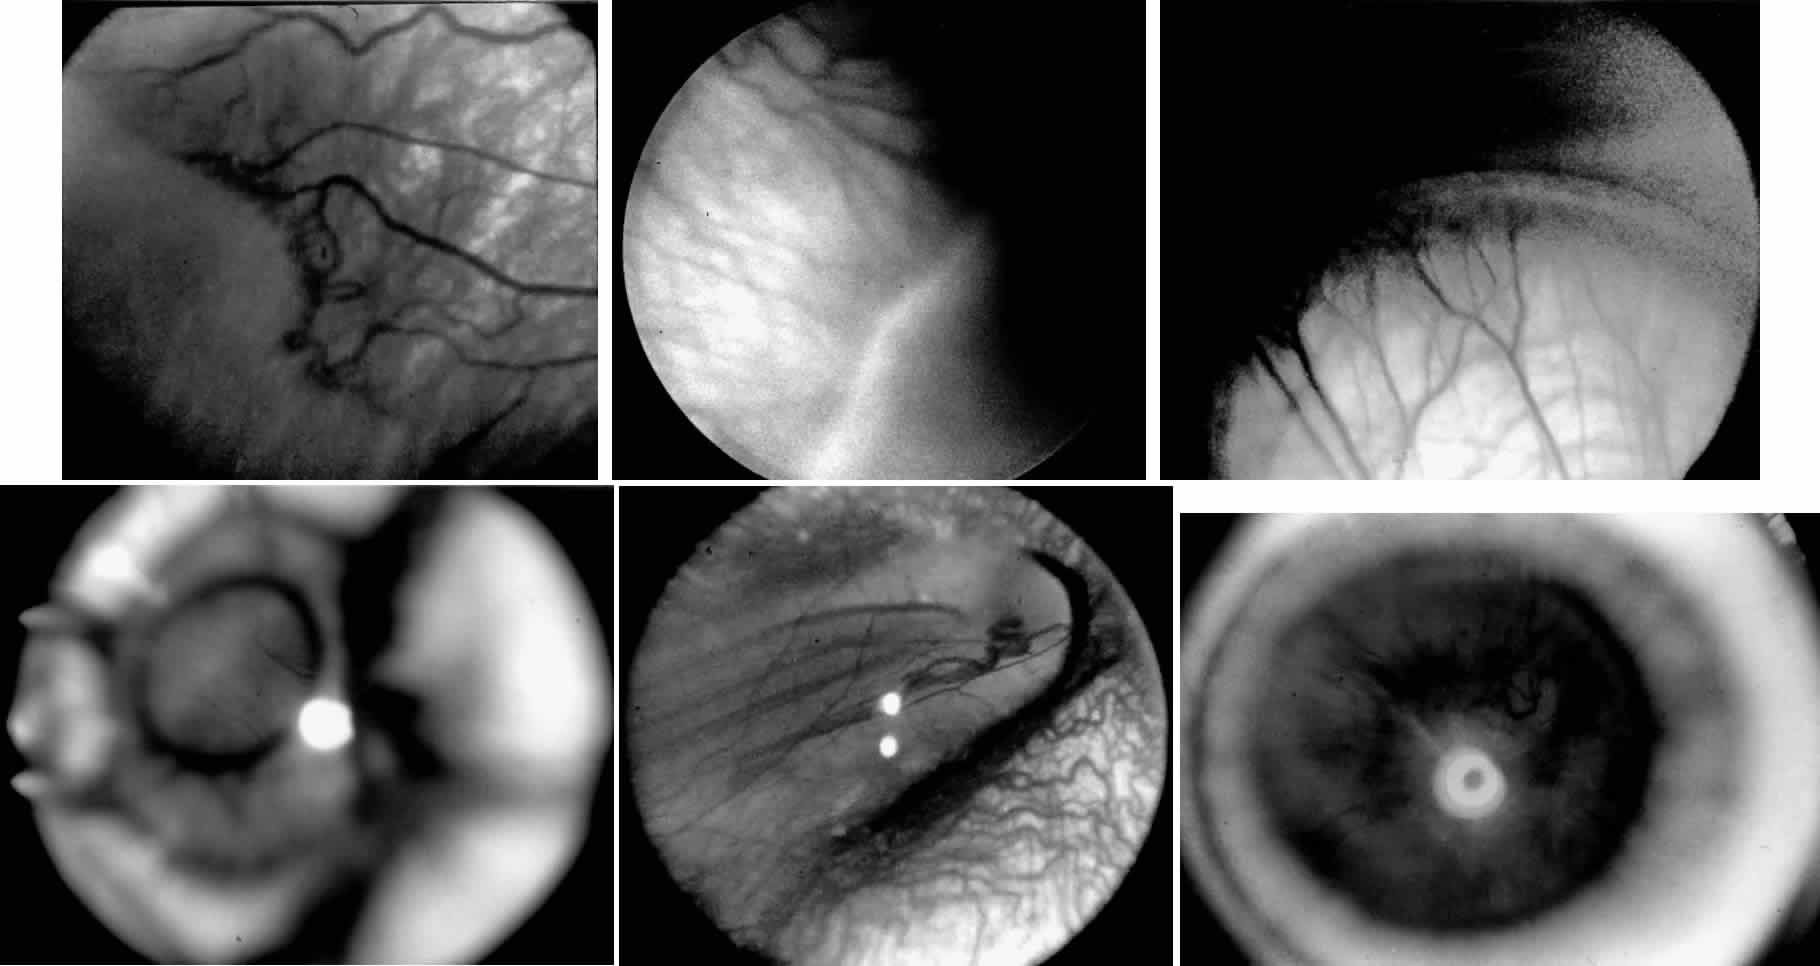

ROP accounts for a large number of retinal detachments in the pediatric

population. The International Classification of Retinopathy of Prematurity

helped greatly to improve communication about, and consequently

treatment of, ROP. It describes affected eyes in terms of stage, zone, and

absence or presence of plus disease18 (Figs. 1, 2, and 3). Screening of premature infants is an important feature in the care of

ROP, which is perhaps the most significant and enduring finding of the

Cryotherapy for Retinopathy of Prematurity Study (Cryo-ROP Study).19

Although several screening protocols have been suggested, we have found that children whose birth weight was 1500 g or less should be screened initially at 4 to 6 weeks after birth, and then every 2 weeks until they reach retinal vascular maturity, which is when nasal vessels in the horizontal meridian have grown to within 1 disc diameter of the ora serrata. During that time, if a child shows threshold disease as defined by the Cryo-ROP Study, namely five clock-hours of contiguous or eight clock-hours of discontiguous neovascularization (stage 3 ROP with plus disease), it is recommended that the child have peripheral ablation with either cryotherapy or laser treatment.19 Newer studies have suggested that zone 1 children may require earlier peripheral ablation.20 The child who fails to respond to peripheral ablation may require further surgical intervention. Two large series reported that scleral buckling for stages 4A and 4B retinal detachments resulted in a retinal reattachment rate of approximately 70%.21,22 These studies were both retrospective; however, they did show a strong trend toward a higher reattachment rate with scleral buckling than the natural history of these detachments, which have a 55% chance of progression of retinal detachment from stage 4 to stage 5 ROP.23 When first assessing a child's retinal detachment, one must judge the amount of effusive versus tractional detachment (Figs. 4 and 5). Scleral buckling would be considered for the child who shows a predominately effusive stage 4B detachment as opposed to a stage 4 predominately tractional detachment, for which lens-sparing vitrectomy may be recommended.24 For a child who has a great deal of retrolenticular touch, lensectomy/ vitrectomy and membrane peeling would be recommended. It appears that the “window” for lens-sparing vitrectomy may be rather brief. In one series, the postconceptual age of the lens-sparing vitrectomized eyes was 42.6 weeks, as opposed to 46.9 weeks for eyes that needed lensectomy/vitrectomy and membrane peeling. This small time difference in the postconceptual age shows the often rapid evolution of this detachment from one in which the lens is salvageable to one in which the lens is unsalvageable. This highlights the need for timely screening of eyes, identification of eyes with progressive disease, and rapid intervention.25